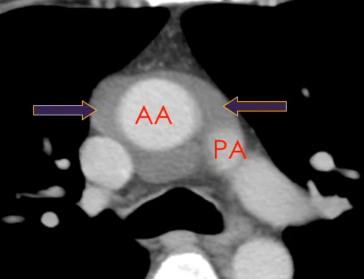

Sinus Transverse